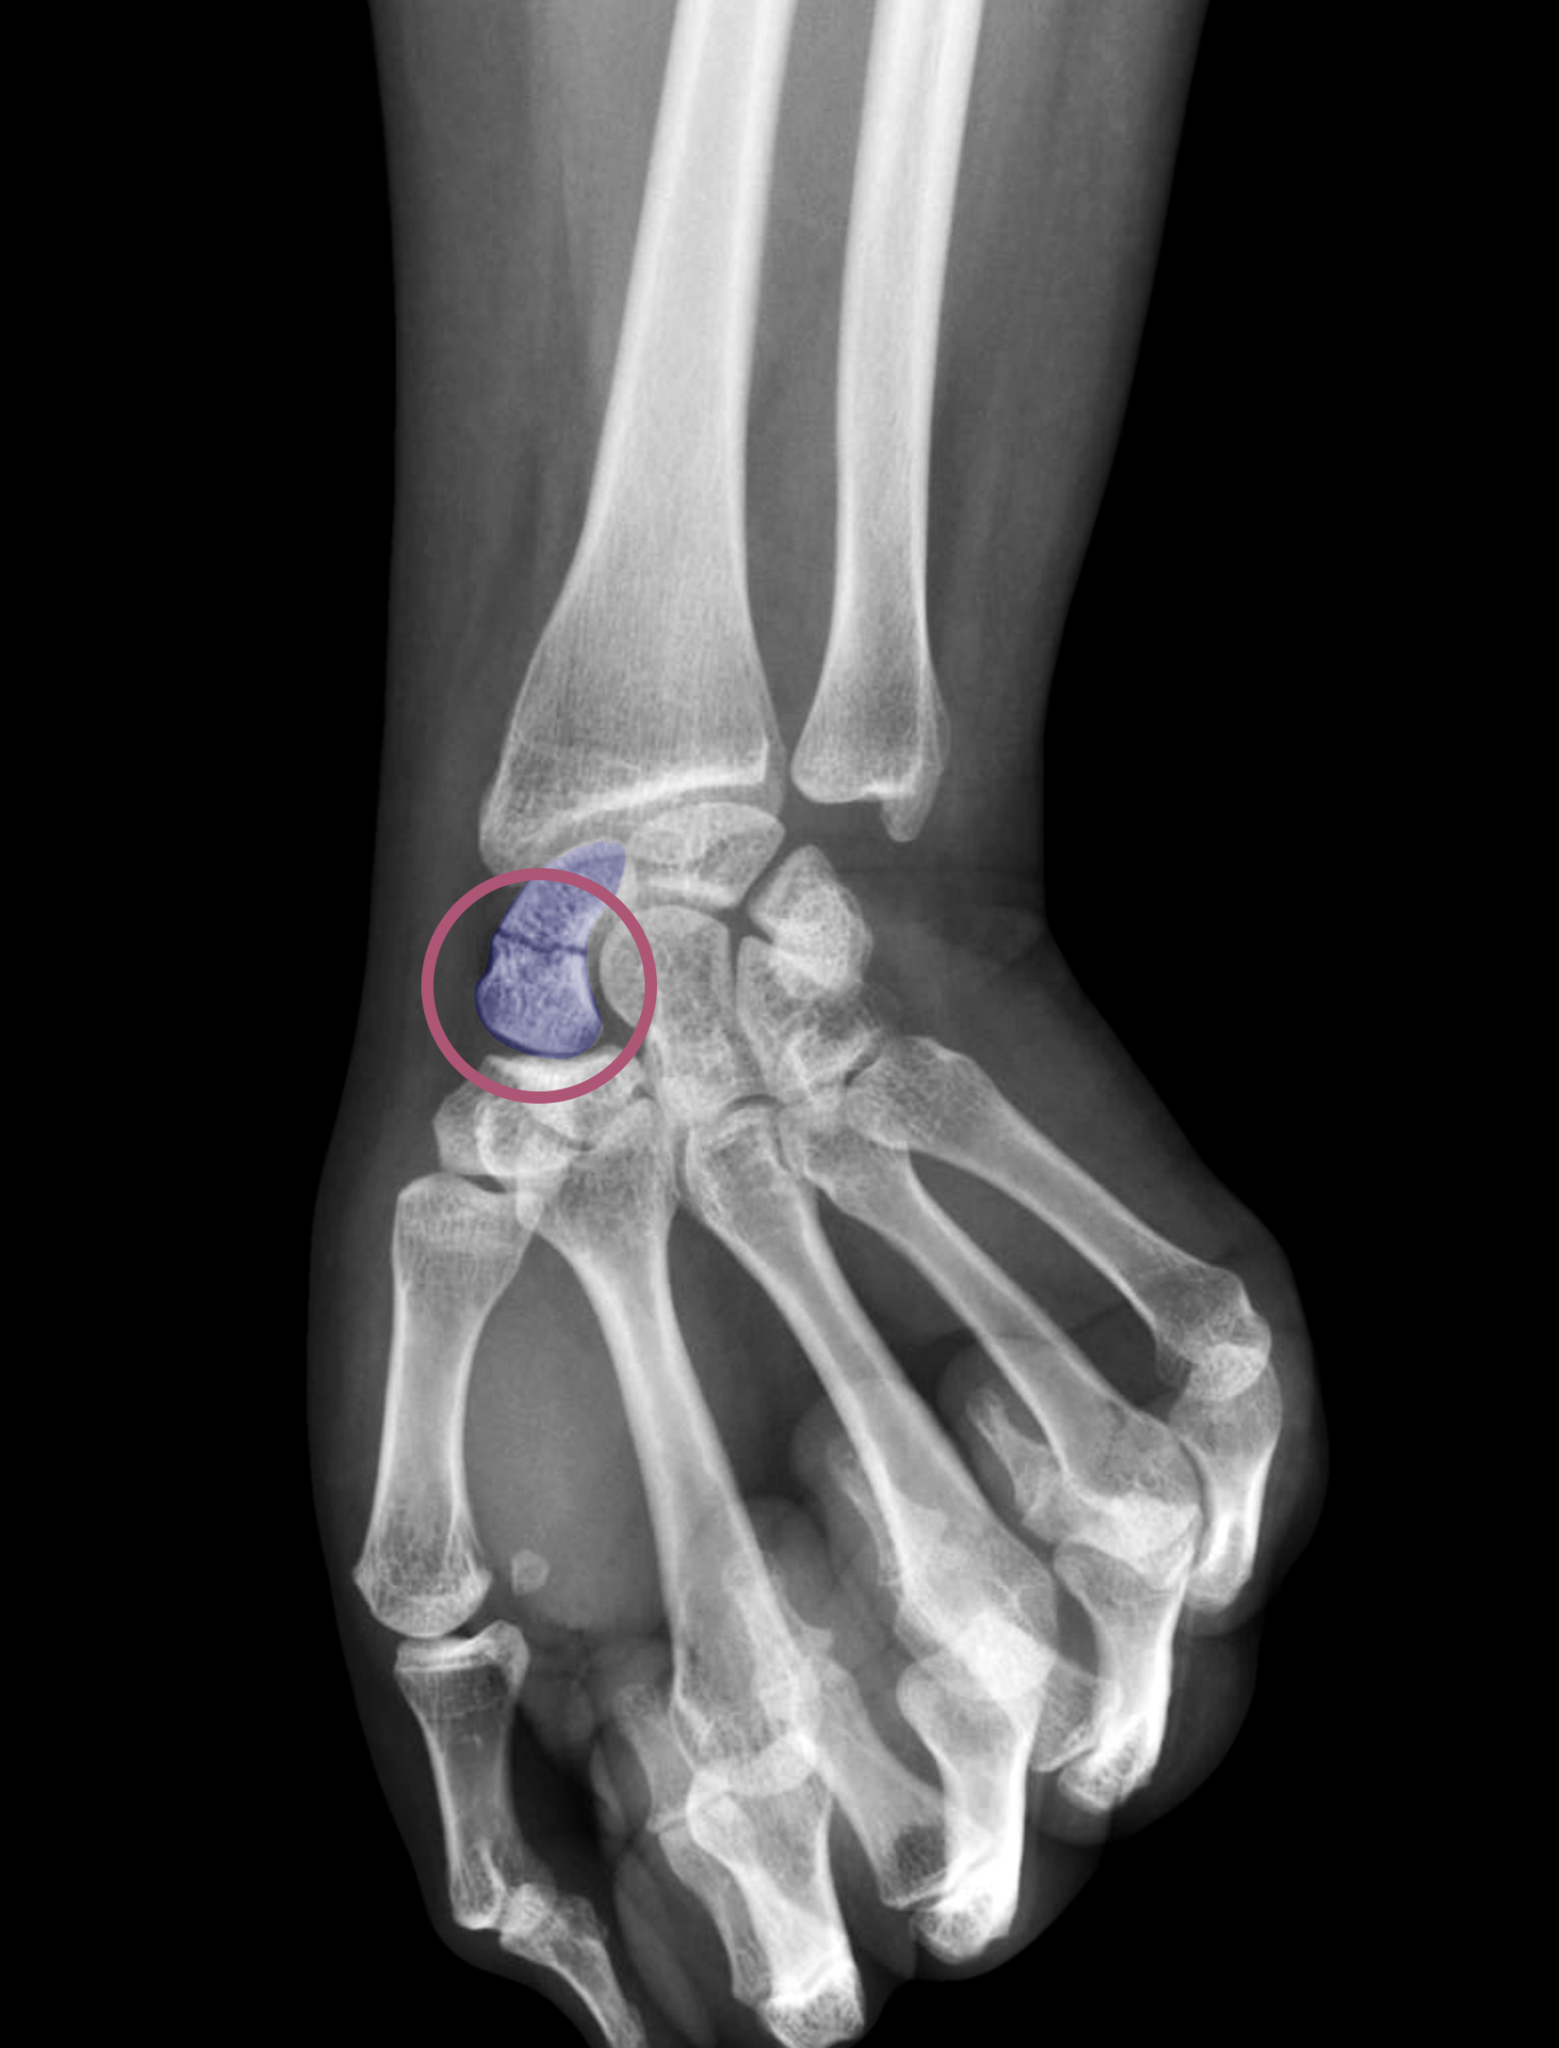

Source: lentumdne.pages.dev Fracture du scaphoïde Paris Clinique Docteur Gilles Cohen , Une étude a constaté que les plâtres en cas de fracture du scaphoïde génaient la conduite automobile Quel est le temps de guérison et consolidation d'une fracture du scaphoïde au pied ? Déjà, soyez rassuré : les fractures de l'os naviculaire récupèrent généralement bien

Source: mestadbyuv.pages.dev Fracture du scaphoïde Clinique du sport , Ce petit os, situé à la base du poignet, joue un rôle crucial dans la mobilité et la fonction de la main Le délai de consolidation varie en fonction de la localisation de la fracture

Source: tostaquieji.pages.dev Fracture clavicule Clavicule cassée Temps de guérison Conseil , Le délai de consolidation varie en fonction de la localisation de la fracture Le scaphoïde est l'un des 8 os constitutifs du carpe, à la base du poignet, et ses fractures sont extrêmement fréquentes